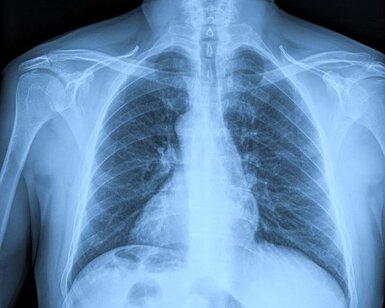

Medical X-ray

Successful Metrology Partnership project workshop on X-ray imaging dosimetry

2024-12-18

Providing the metrology required to ensure patient safety during medical X-rays more